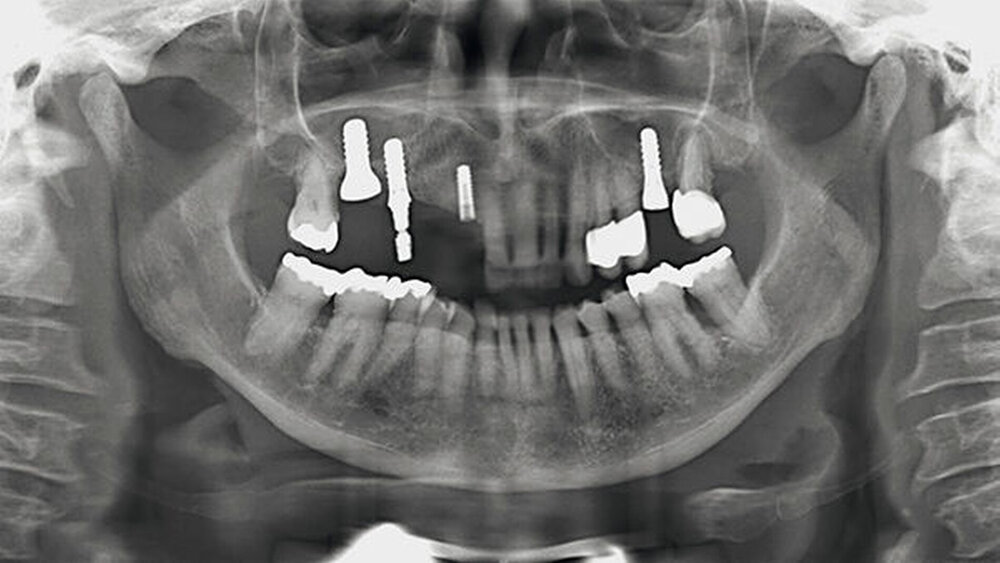

Dr. Sebastian Schwindling (Universität Heidelberg) ist Young-Esthetics-Preisträger 2017. Sein Fall ist komplex: die Gesamtrehabilitation eines parafunktionell vorgeschädigten Gebisses. "Selbst erfahrene Zahnärzte würden sich damit nicht leicht tun", heißt es aus der Jury. Hier stellt der Preisträger seine Arbeit vor.